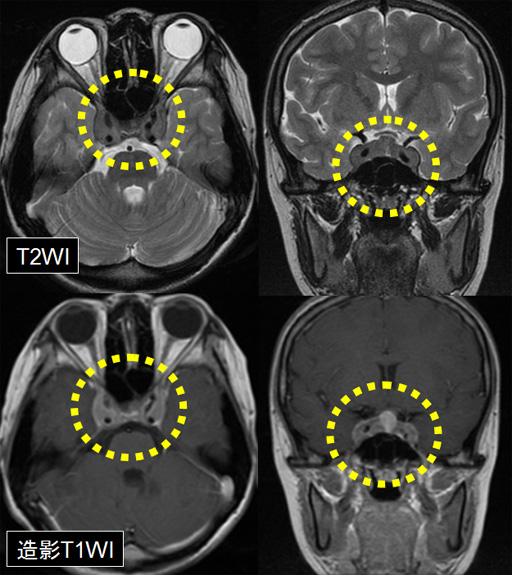

頭部造影MRI

- 海綿静脈洞部にT2WIにて低信号の腫瘤あり。腫瘤は均一な増強効果あり。